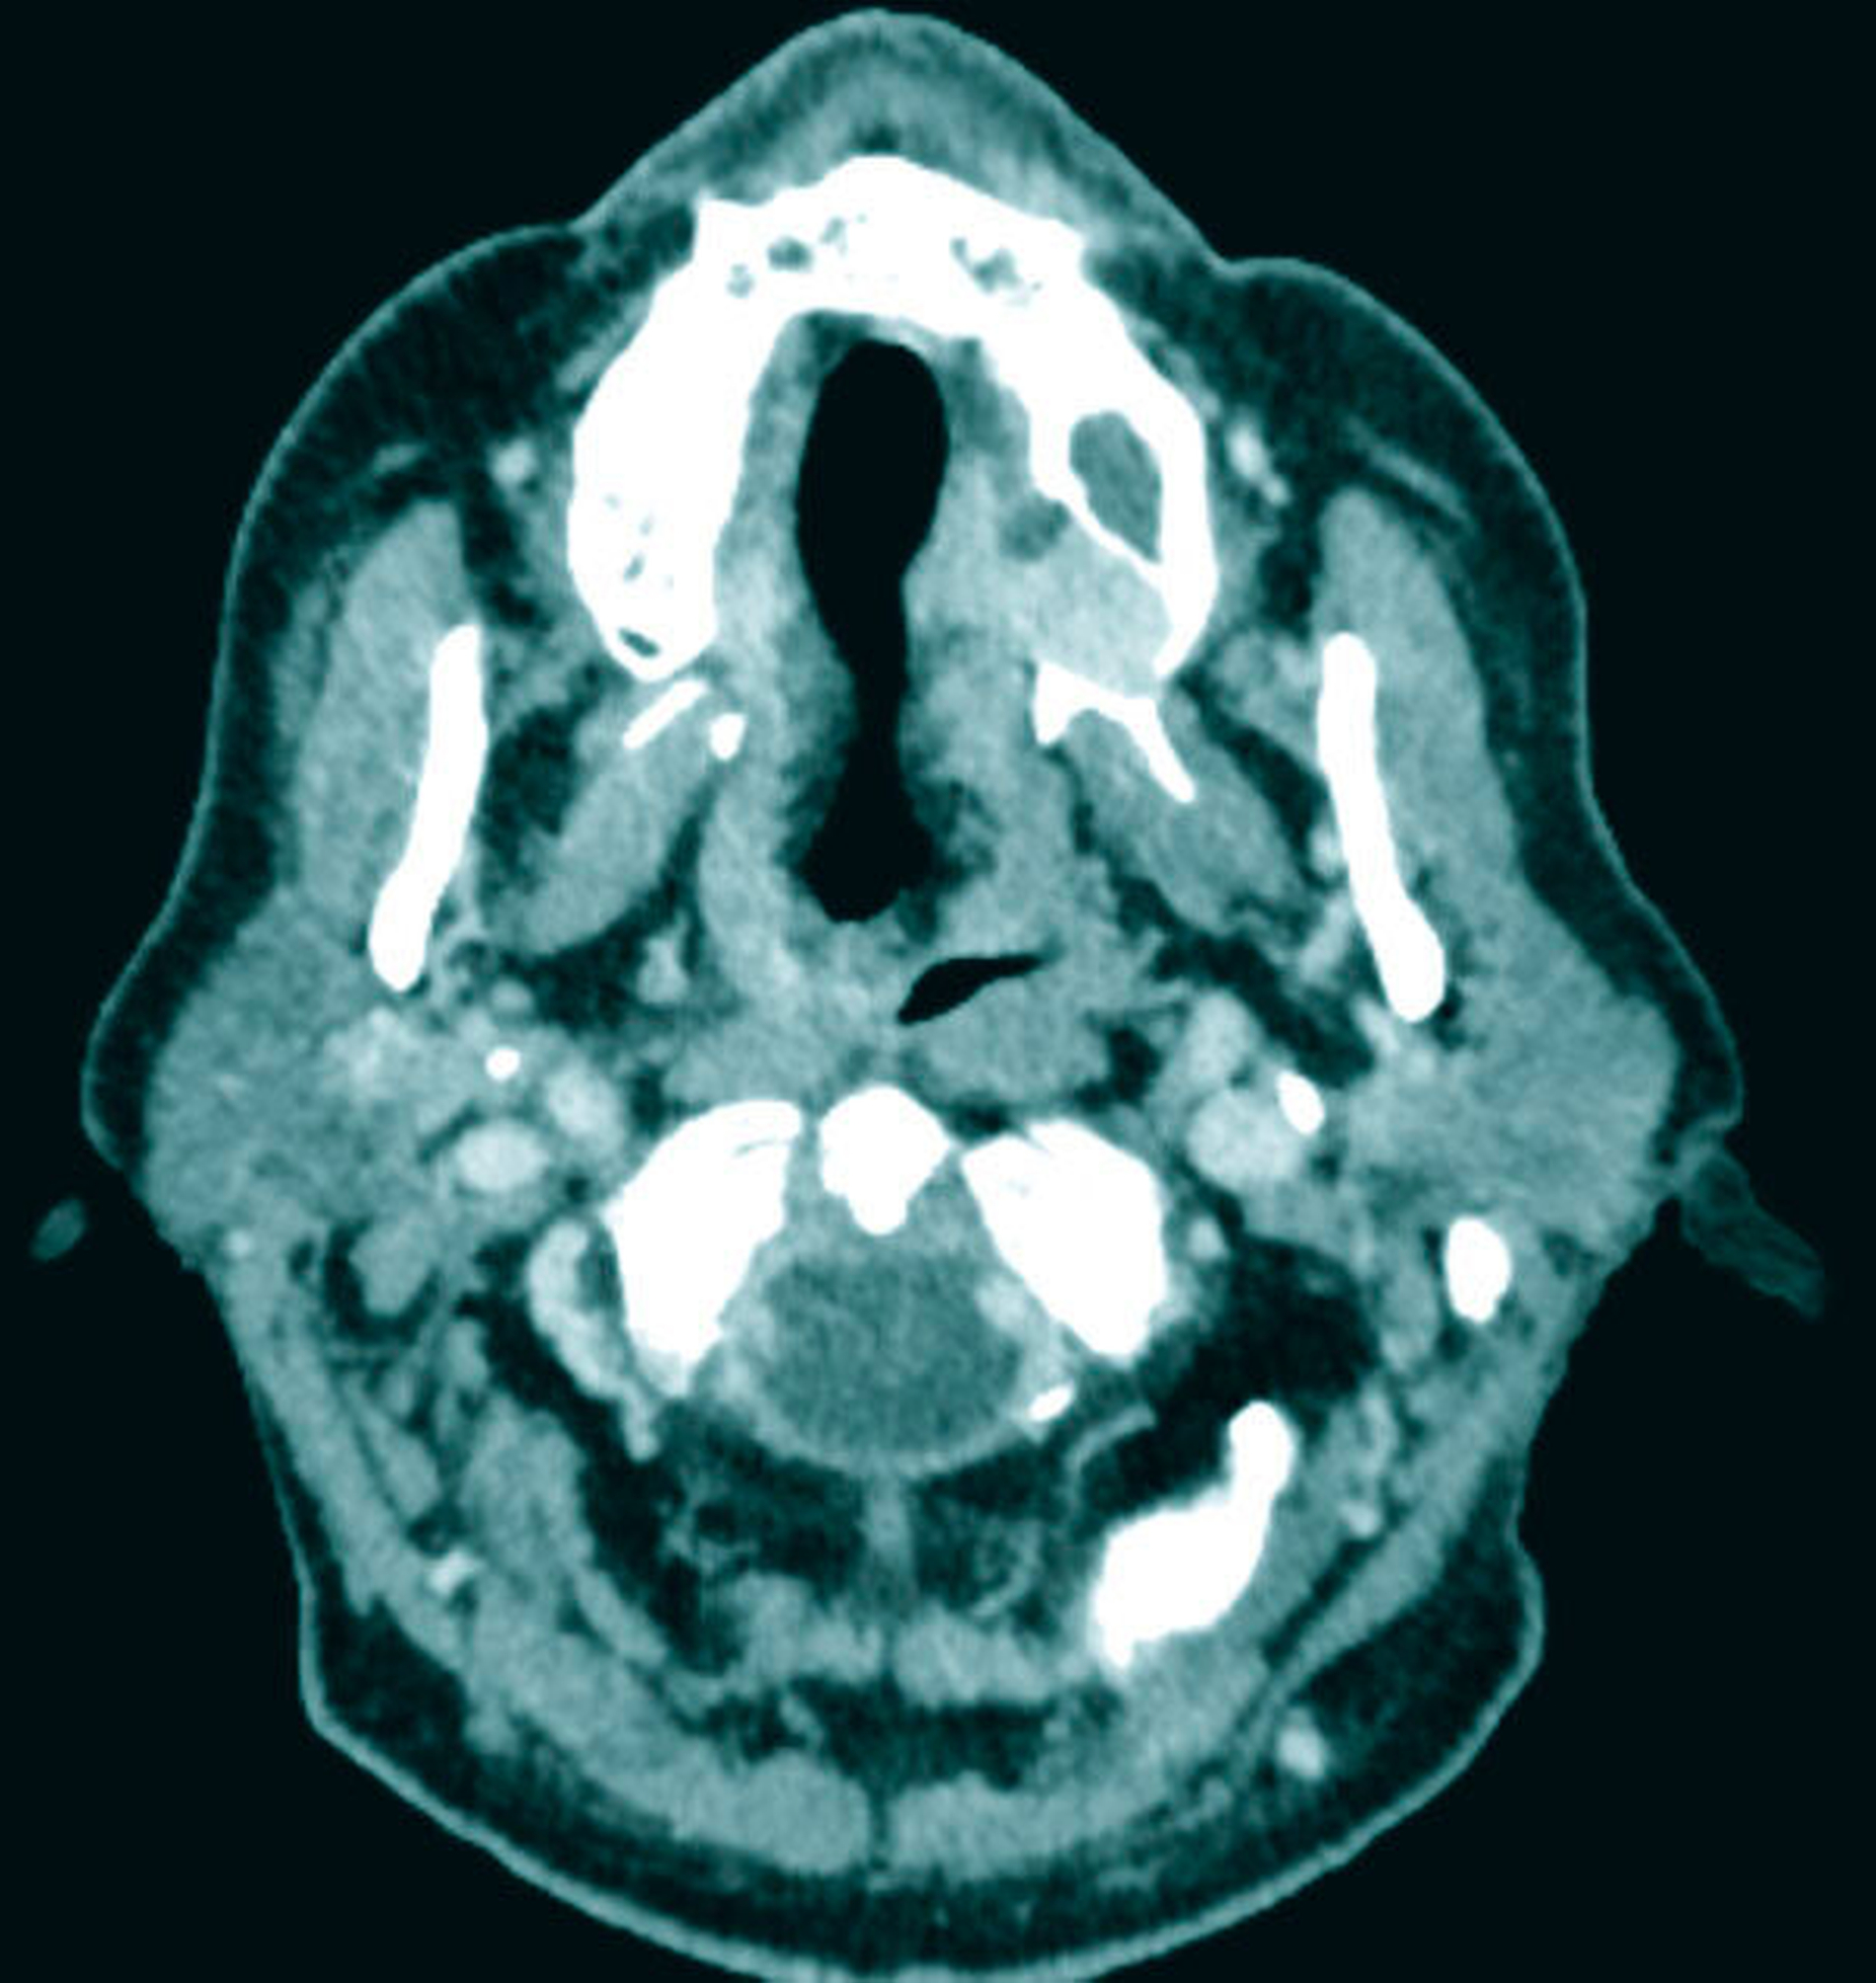

Zum Zeitpunkt der Untersuchung zeigte sich im linken Oberkiefer palatinal regio 26/27 ein livider braun-rötlicher Tumor von etwa zwei Zentimeter Größe mit Verdrängung der fixierten Gingiva nach krestal. Nach palatinal-medial war das Bindegewebe unter reizloser Schleimhaut aufgetrieben (Abbildung 1). In der Bildgebung mittels Panoramaschichtaufnahme zeigte sich in der interessierenden Region eine Verschattung der linken basalen Kieferhöhle mit Auflösung des krestalen Knochens im Molarenbereich. Des Weiteren war ein retinierter Zahn 48 und ein horizontal-vertikaler Knochenabbau bei bekannter Parodontitis zu erkennen (Abbildung 2). Zur weiteren Diagnostik wurde eine Computertomografie des Kopfes und bei Verdacht auf mögliche Metastasierung der vorbekannten Malignome eine Computertomografie des Thorax und Abdomens durchgeführt. Hierbei zeigte sich die bereits diagnostizierte Raumforderung im Bereich der linken basalen Kieferhöhle mit partieller Auflösung des molarennahen Knochens und einer weichteildichten Raumforderung im Bereich der basalen Kieferhöhle. Die kranialen Anteile der Kieferhöhle waren belüftet (Abbildung 3). Ein Anhalt für eine Metastasierung oder ein Rezidiv des Urothel- bzw. Prostatakarzinoms bestand nicht. In dem durch eine Inzisionsbiopsie in Lokalanästhesie entnommenem Gewebe zeigte sich histologisch eine teils glandulär, teils kribriform konfigurierte epitheliale Proliferation mit teils basophilem Stroma. Es lag eine deutliche Positivität für CK7 und S100 ohne Färbereaktion für CK5/6 vor. Somit entsprach der Befund dem eines kanalikulären Adenoms. Der Tumor wurde in Intubationsnarkose entfernt. Zur Kieferhöhle bestand eine dünne knöcherne Abgrenzung, die belassen wurde. Eine endoskopische Untersuchung über den mittleren Nasengang zeigte bis auf zwei kleinen Schleimretentionszysten oberhalb der Läsion – die jeweils entfernt wurden – keine weiteren Auffälligkeiten. Der Defekt wurde durch eine Einlagerung des Bichat’schen Fettkörpers und eines Mukoperiost-Lappens von vestibulär gedeckt. Die finale histologische Beurteilung bestätigte die Diagnose und eine vollständige Entfernung. Nach einem unkomplizierten postoperativen Heilungsverlauf zeigte der Patient in der klinischen Nachsorge nunmehr sechs Monate nach Operation keinen Anhalt für ein Rezidiv.

Zur Diagnostik kann entweder eine Magnetresonanztomografie oder bei knöcherner Beteiligung eine Computertomografie durchgeführt werden. Bei reinen Weichgewebstumoren der Oberlippe oder Wange kann auch eine Sonografie ausreichend sein. Das radiologische Bild entspricht einer gut abgrenzbaren Weichteilmasse mit mitunter lokal aggressivem Wachstum und knöcherner Destruktion [Smullin et al., 2004].